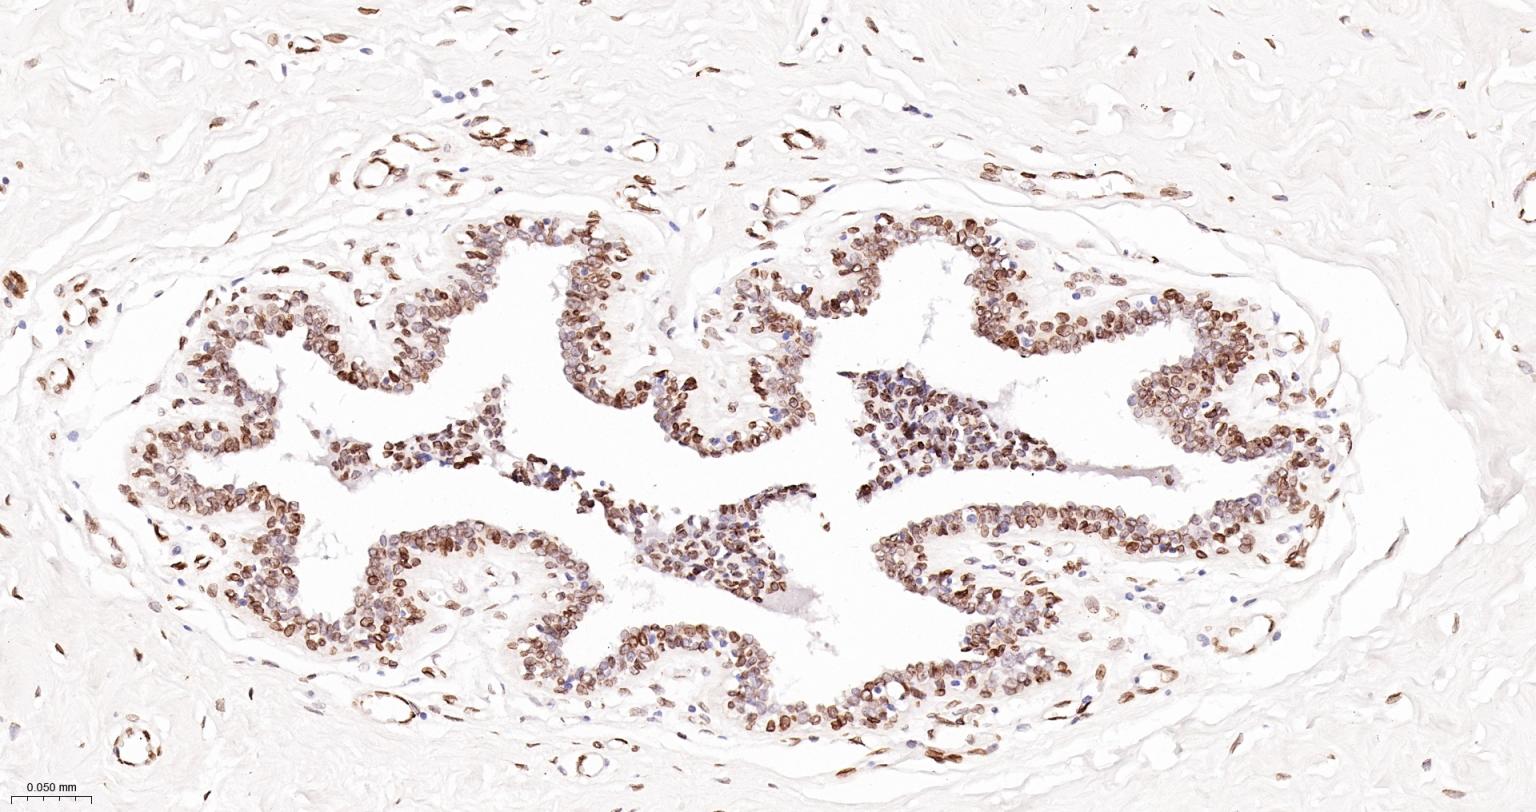

Paraformaldehyde-fixed, paraffin embedded Human Breast; Antigen retrieval by boiling in sodium citrate buffer (pH6.0) for 15 min; The section was incubated with Lamin A/C Monoclonal Antibody, Unconjugated (bsm-51683M) at 1:100 overnight at 4°C, followed by conjugation to the bs-40296G-HRP and DAB (C-0010) staining.